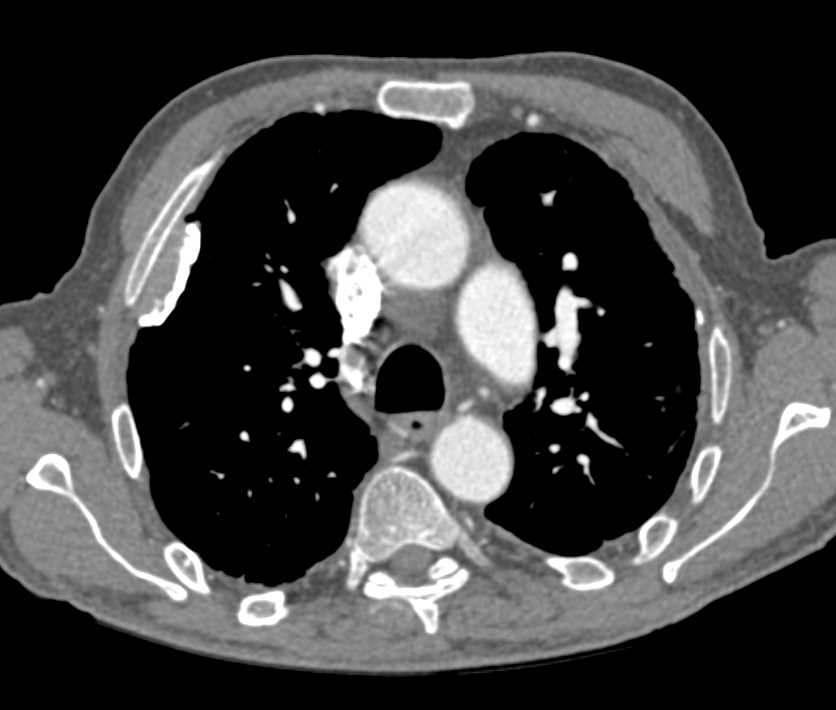

- HRCT (Goldstandard): „honigwabenartige“ Veränderungen (v. a. bei IPF)

| Idiopathische Lungenfibrose (IPF) | unklar (idiopathisch) | Belastungsdyspnoe, trockener Husten, Trommelschlegelfinger | HRCT: Honigwaben, basal, subpleural; Lufu: restriktiv | Antifibrotika(Pirfenidon, Nintedanib), evtl. Lungentransplantation | Respiratorische Insuffizienz, pulmonale Hypertonie |